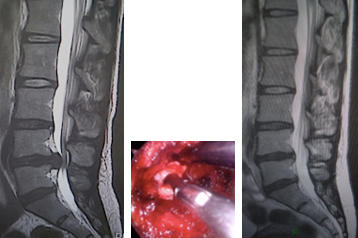

(左)術前MRI 第4/5腰椎に椎間板ヘルニアを認めます。

(中)内視鏡下(MED)にヘルニアを摘出しました。

(右)術後MRI 第4/5腰椎の椎間板ヘルニアが消失しています。